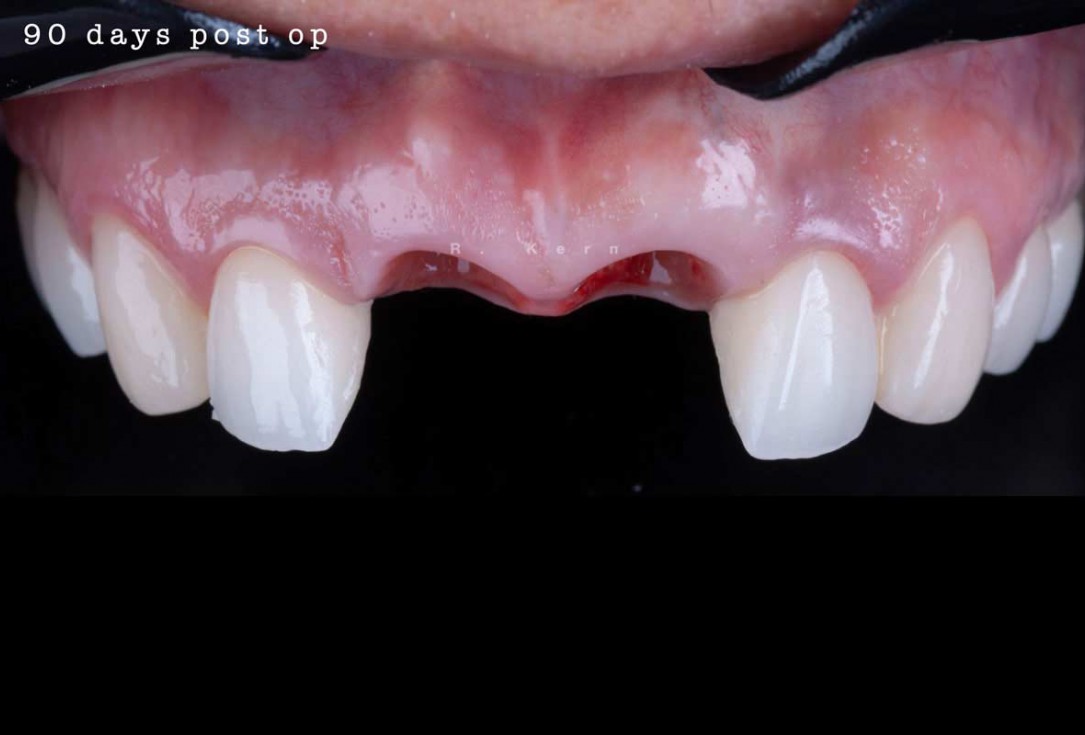

09/12 - Situation 90 days post-operative, occlusal view

Immediate implant placement and periimplant bone augmentation using cerabone® - Dr. R. Kern